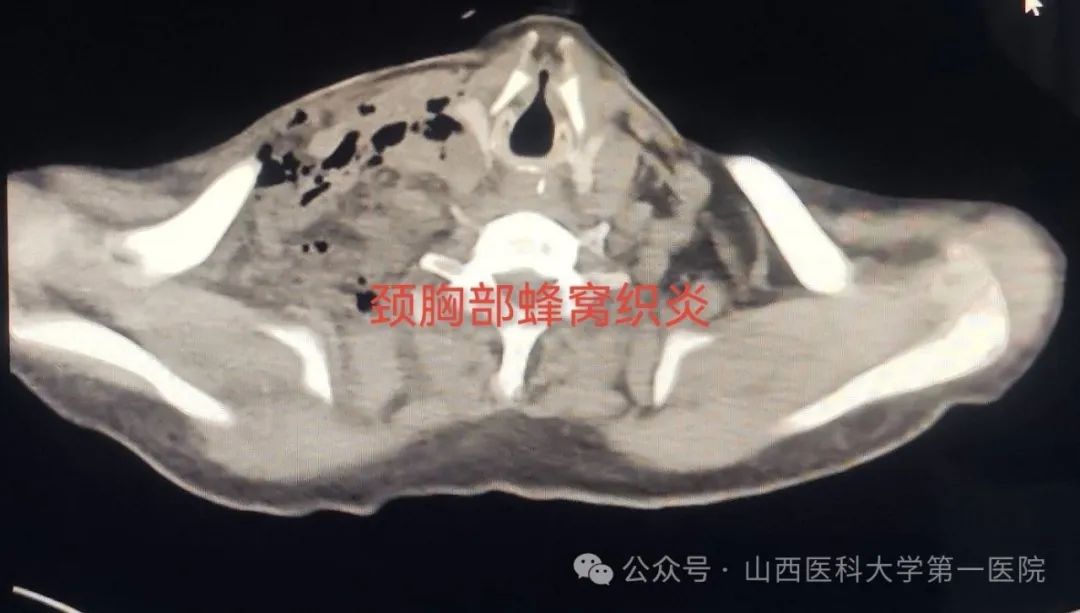

患者误咽枣核后出现咽喉疼痛、吞咽疼痛,未引起本人重视,5天后自行呕吐出枣核异物,次日出现颈部疼痛,伴发热、咳嗽咳痰、痰中带血丝,声音沙哑,症状逐渐加重,于当地医院治疗后病情并未得到有效控制,咽喉疼痛进一步加重,同时发现一侧颈部肿胀伴有高热,当地医院认为病情危重建议转入山医大一院。入院后,耳鼻咽喉-头颈外科医生完善各项辅助检查,积极给予消炎消肿抗感染药物治疗,但是颈部肿胀逐渐明显,患者一侧颈部已有大面积红肿、膨隆,皮肤出现捻发音,颈部超声检查及颈部CT检查提示:颈部严重感染,脓肿形成,纵隔感染,脓胸。若不及时处置很有可能造成败血症、脓毒血症,引发感染性休克而危及生命。

据皇甫辉教授介绍,患者所患为颈部蜂窝组织炎,而急性蜂窝组织炎是皮下、筋膜下、肌间隙或深部蜂窝组织的急性弥漫性化脓性感染,致病菌有溶血性链球菌、金黄色葡萄球菌和厌氧菌,溶血性链球菌导致急性蜂窝组织炎由于链激酶和透明质酸酶作用病变扩展迅速,可以引起败血症;患者由于高龄、心肺功能差、抵抗力差,蜂窝组织炎如果不及时处理极有可能造成生命危险,若感染炎症向下蔓延播散,引起咽喉部急性炎症、咽喉脓肿,可发生上呼吸道阻塞并迅速出现呼吸困难;如炎症扩散经咽侧壁侵入咽旁隙,则形成咽旁间隙脓肿,少数患者可并发颈动脉鞘感染、颈静脉血栓、脓毒血症、化脓性颈淋巴结炎等严重并发症发生。

尽管患者高龄,食管穿孔后并发颈部蜂窝组织炎,出现颈部脓肿、纵隔脓肿、脓胸、脓毒血症、肺部感染、心律失常、房颤、肺动脉高压、左右心房扩大、低蛋白血症、水电解质与酸碱平衡紊乱、下肢静脉血栓形成、真菌感染、耐药菌株产生等危重情况,医护人员克服一切困难,及时调整医疗与护理方案,消炎消肿抗感染、颈部切开引流、胸腔闭式引流等,矫正水、电解质紊乱与酸碱紊乱,对症治疗等,经过两个多月的精心呵护,患者最终痊愈出院。